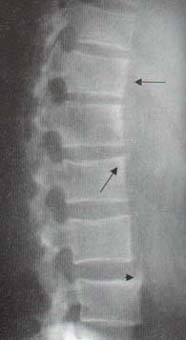

Sindesmofito no marginal: en este caso la calcificación se origina en la porción media del cuerpo vertebral extendiéndose hasta la región equivalente del cuerpo adyacente dejando una zona radiolúcida entre los cuerpos y la calcificación. Este tipo de calcificación puede comprometer más de dos niveles de la columna (Figura 2).

Figura 2. Sindesmofito no marginal en un paciente con Síndrome de Reiter.

Obsérvese que sale de la mitad del cuerpo vertebral superior y llega al adyacente,

por debajo de la esquina del mismo.